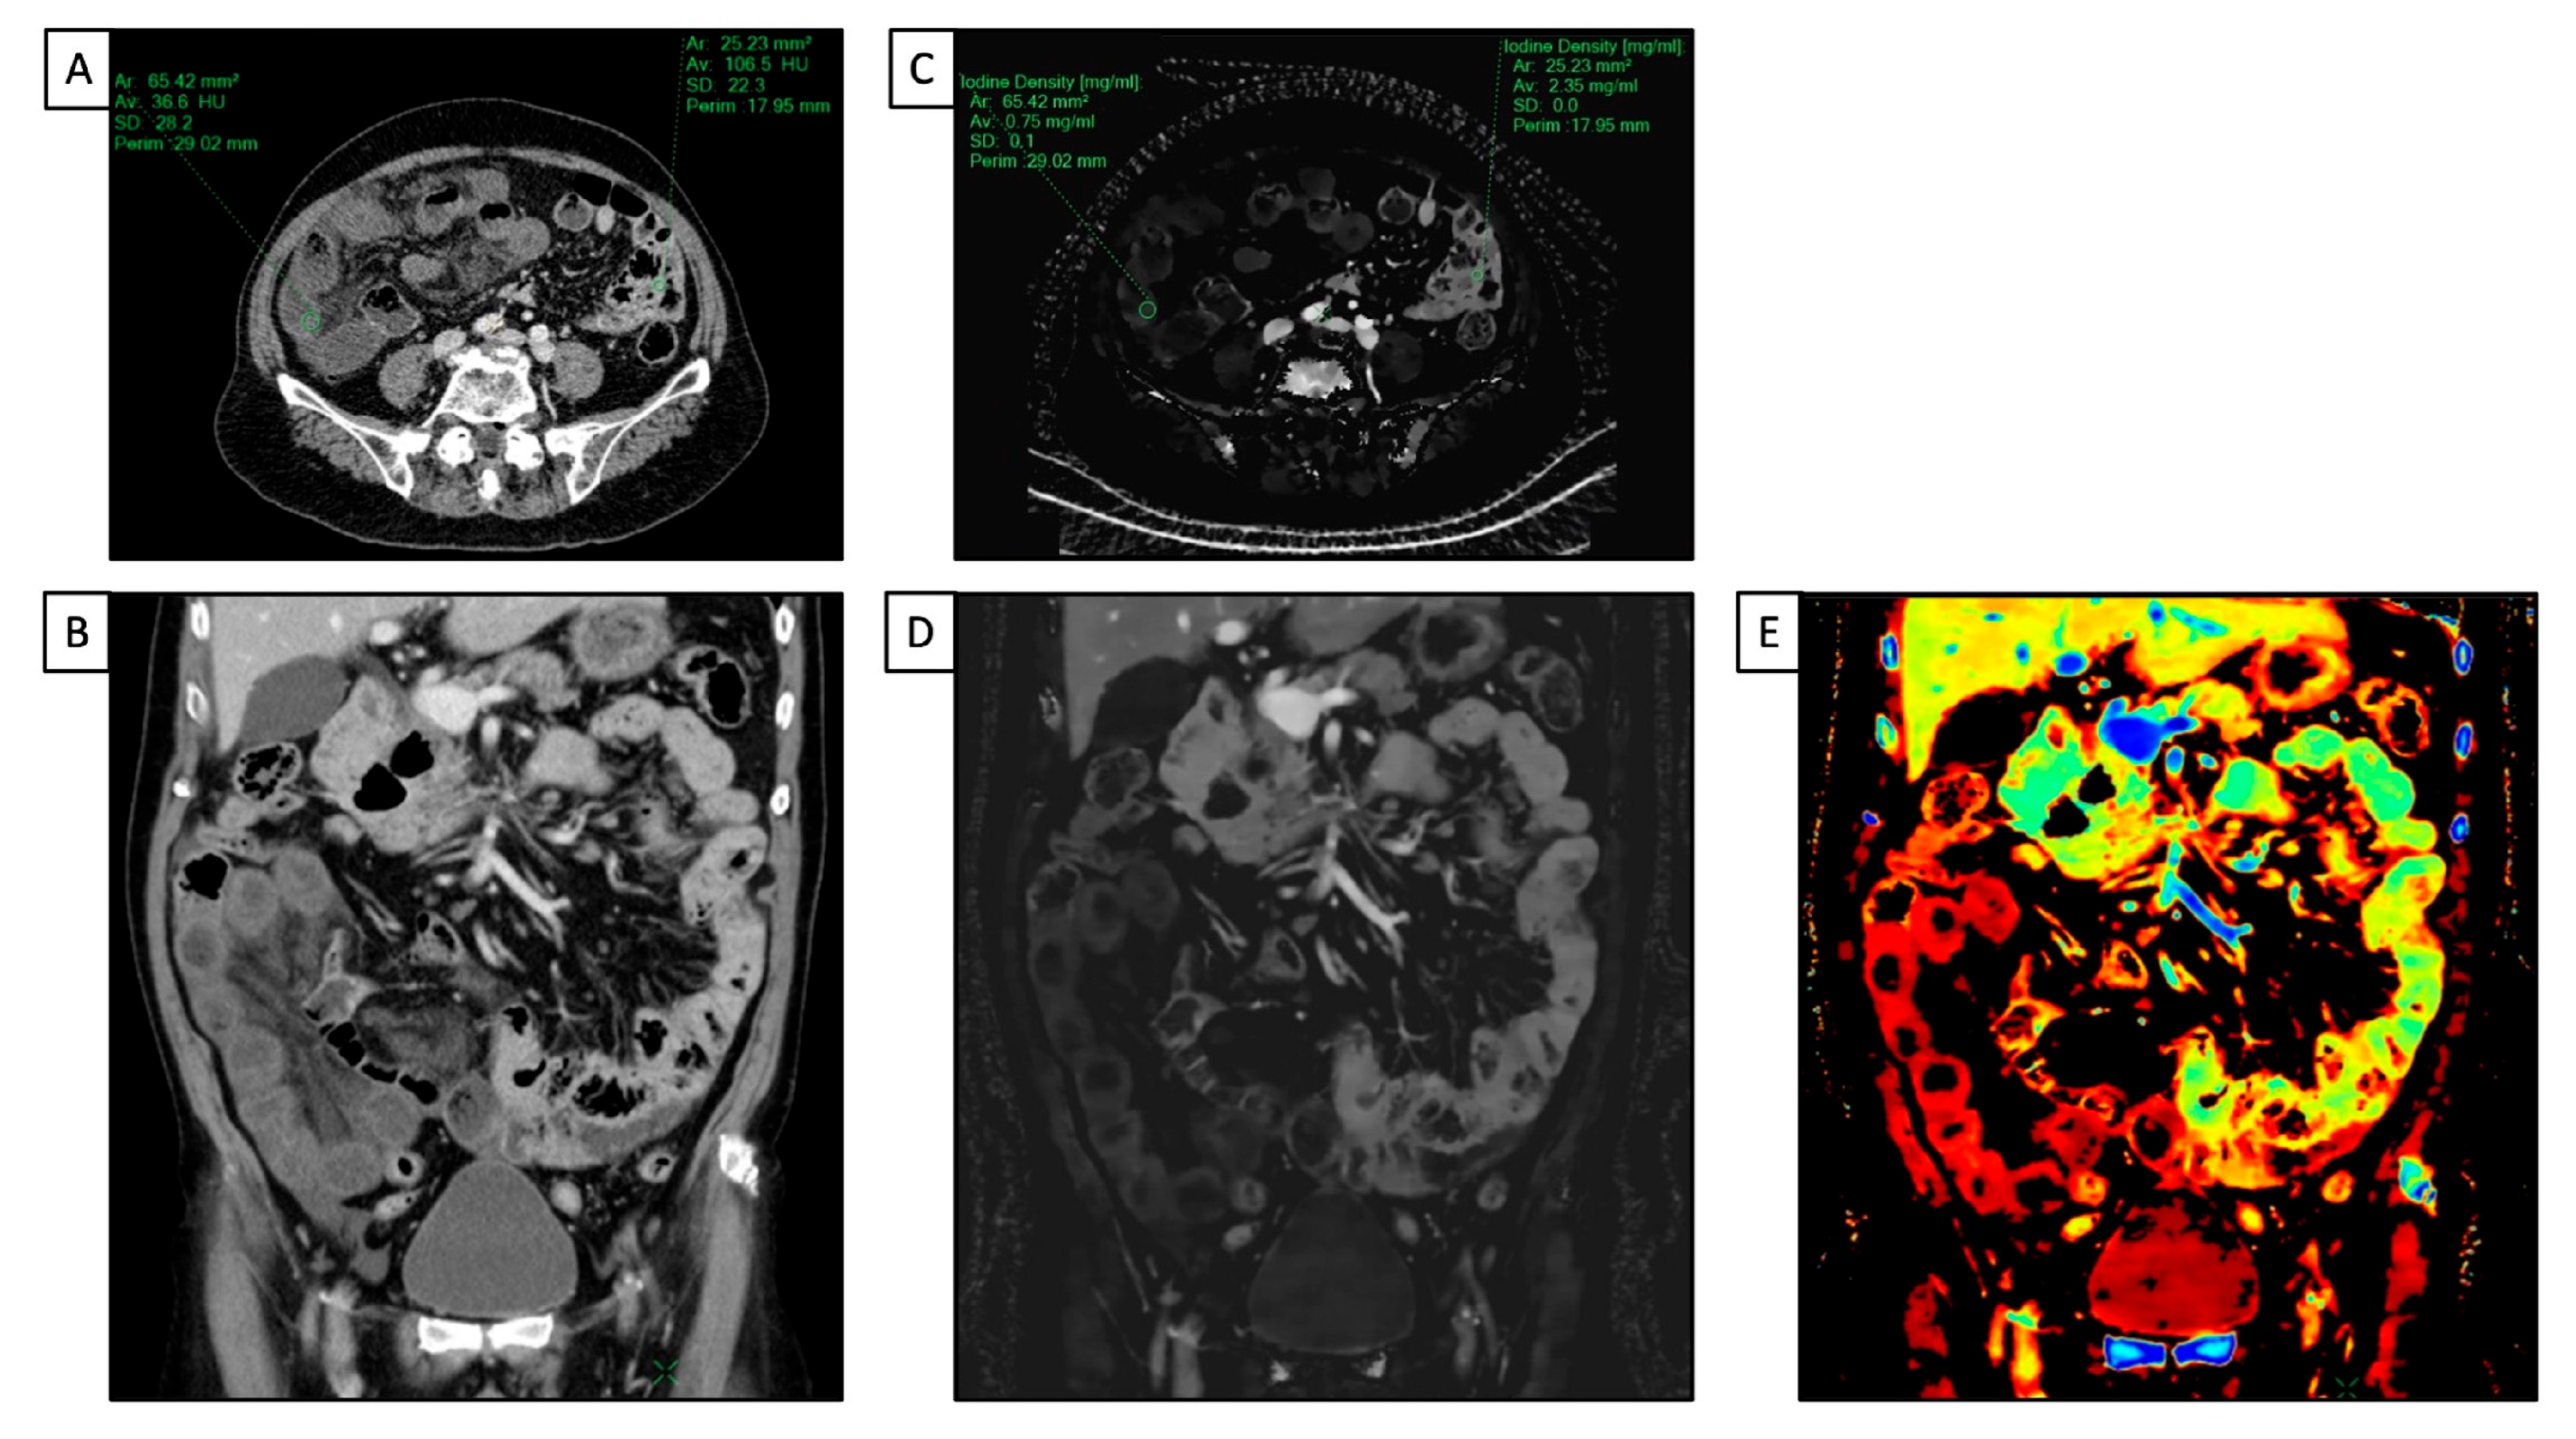

- Chen, W.; Ye, Y.; Zhang, D.; Mao, L.; Guo, L.; Zhang, H.; Du, X.; Deng, W.; Liu, B.; Liu, X. Utility of Dual-Layer Spectral-Detector CT Imaging for Predicting Pathological Tumor Stages and Histologic Grades of Colorectal Adenocarcinoma. Front. Oncol. 2022, 12, 1002592. [Google Scholar] [CrossRef]

- Wang, G.; Fang, Y.; Wang, Z.; Jin, Z. Quantitative Assessment of Radiologically Indeterminate Local Colonic Wall Thickening on Iodine Density Images Using Dual-Layer Spectral Detector CT. Acad. Radiol. 2021, 28, 1368–1374. [Google Scholar] [CrossRef] [PubMed]